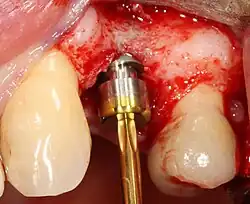

The implant fixture is turned into the osteotomy. Ideally, it is completely covered by bone and has no movement within the bone.

Placing the implant

Most implant systems have five basic steps for placement of each implant:[28]: 214–221

1. Soft tissue reflection: An incision is made over the crest of bone, splitting the thicker attached gingiva roughly in half so that the final implant will have a thick band of tissue around it. The edges of tissue, each referred to as a flap, are pushed back to expose the bone. Flapless surgery is an alternate technique, where a small punch of tissue (the diameter of the implant) is removed for implant placement rather than raising flaps.

2. Drilling at high speed: After reflecting the soft tissue, and using a surgical guide or stent as necessary, pilot holes are placed with precision drills at highly regulated speed to prevent burning or pressure necrosis of the bone.

3. Drilling at low speed: The pilot hole is expanded by using progressively wider drills (typically between three and seven successive drilling steps, depending on implant width and length). Care is taken not to damage the osteoblast or bone cells by overheating. A cooling saline or water spray keeps the temperature low.

4. Placement of the implant: The implant screw is placed and can be self-tapping;[50]: 100–102  otherwise, the prepared site is tapped with an implant analog. It is then screwed into place with a torque controlled wrench[54] at a precise torque so as not to overload the surrounding bone (overloaded bone can die, a condition called osteonecrosis, which may lead to failure of the implant to fully integrate or bond with the jawbone).

5. Tissue adaptation: The gingiva is adapted around the entire implant to provide a thick band of healthy tissue around the healing abutment. In contrast, an implant can be "buried", where the top of the implant is sealed with a cover screw and the tissue is closed to completely cover it. A second procedure would then be required to uncover the implant at a later date.